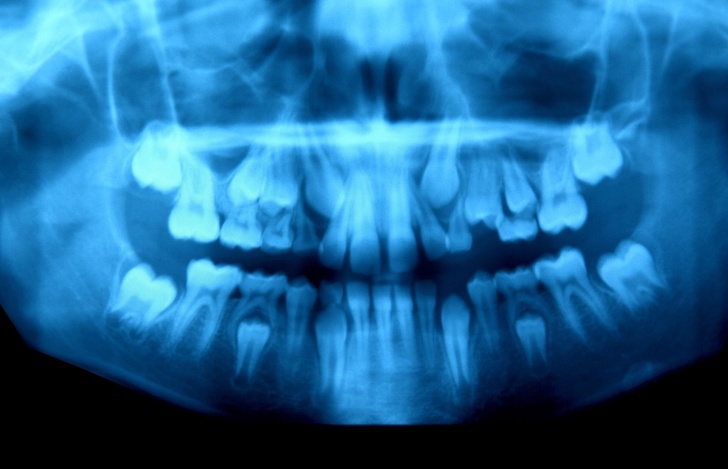

16. Щелепа 10-річного хлопчика, у якого відбувається заміна молочних зубів на постійні